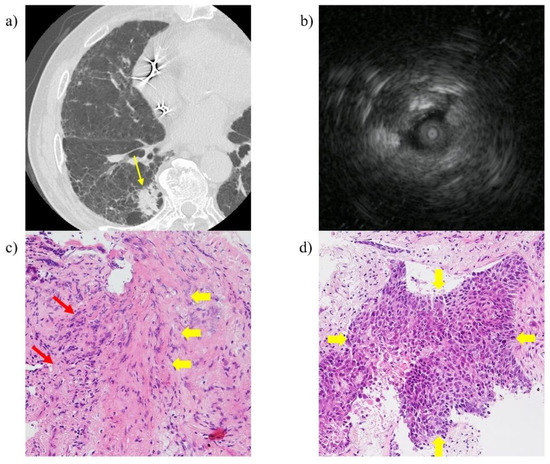

Endobronchial Ultrasonography with a Guide Sheath Transbronchial Biopsy for Diagnosing Peripheral Pulmonary Lesions within or near Fibrotic Lesions in Patients with Interstitial Lung Disease

2.2. EBUS-GS TBB Procedure

3.2. Diagnostic Yields by Probe Location and Disease Type between PPLs within or near Fibrotic Lesions and Those Distant from Fibrotic Lesions